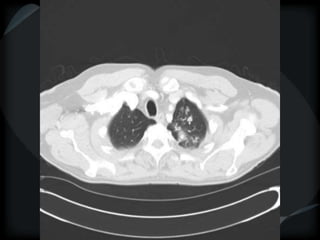

Reticular Pattern - NSIP

inflammation and fibrosis

 Predominantly basilar

 Significant ground glass

 Subpleural sparing low sensitivity, high specificity

 No honeycombing, some cystic change

 Traction Bronchiectasis

Diagnostic accuracy 50%

 Cellular NSIP

 Fibrotic NSIP

 Associated with CVD

 Undifferentiated CVD – T. King

NSIP- cellular

NSIP-fibrotic